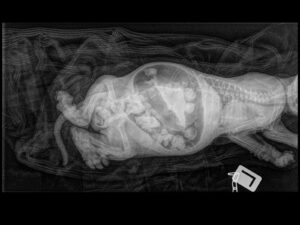

When Victor was born, he looked normal for the first few days. He ate well, grew well, and seemed strong. Then we discovered that he had been born without a normal anal opening. At that moment, we made a decision. We would do everything we could to save him. We believed he could still have a healthy and happy life, and as breeders, we felt it was our responsibility to care for the life we brought into this world.

Because he was still so young, we waited until he was about one month old before surgery. We did not want to risk losing him because of his young age. We brought him to Capital City Animal Emergency Hospital in Ottawa, and we are deeply grateful to Dr. Jeff Biskup, who performed the surgery that gave Victor a functional artificial opening and the chance to enjoy the world fully.

X-Rays